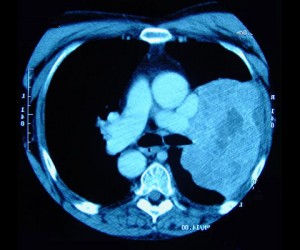

Οι ελικοειδείς τομογραφίες κάνουν λήψη πολλαπλών εικόνων από όλο το στήθος μέσα σε επτά έως δεκαπέντε δευτερόλεπτα, ενώ η απλή ακτινογραφία Χ κάνει λήψη μόνο μιας εικόνας. Οι ερευνητές πάντως επεσήμαναν ότι οι τομογραφίες είναι ακριβότερες και εκθέτουν τους ανθρώπους σε μεγαλύτερη ακτινοβολία, σε σχέση με τις ακτίνες Χ.